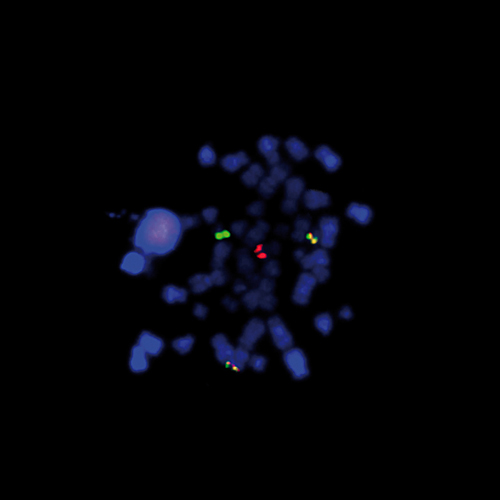

KBI-10504

15q22 / 6q21